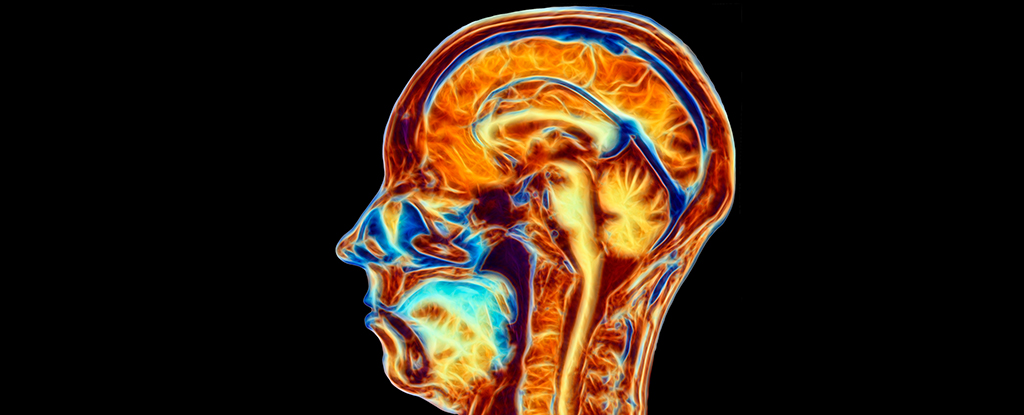

Our brains change more rapidly at various times of our lives, as though life’s clock was ticking faster than usual. Childhood, adolescence and very old age are good examples of this.

Several structures of the brain have been found to change in midlife. The hippocampus, an area critical for forming new memories, is one of them.

It shrinks throughout much of adulthood, and this shrinkage seems to accelerate around the time of middle age. Abrupt shifts in the size and function of the hippocampus during middle age could underlie memory changes like the ones mentioned above.

Ultimately, what allows the brain to carry out its functions are the connections between brain cells – the white matter. These connections mature slowly throughout adulthood, especially the ones connecting areas of the brain that deal with cognitive functions such as memory, reasoning and language.

Interestingly, during middle age, many of them go through a turning point, from gaining volume to losing volume. This means that signals and information cannot be transmitted as fast. Reaction time starts deteriorating around the same time.

Through the white matter connections, brain areas talk to each other and form interconnected networks that can perform cognitive and sensory functions, including memory or vision. While the sensory networks deteriorate gradually throughout adulthood, the cognitive networks start deteriorating faster during middle age, especially those involved in memory.

Much like how highly connected people in society tend to form cliques with each other, brain regions do the same through their connections. This organisation of the brain’s communication allows us to perform some of the complex tasks we might take for granted, such as planning our days and making decisions.